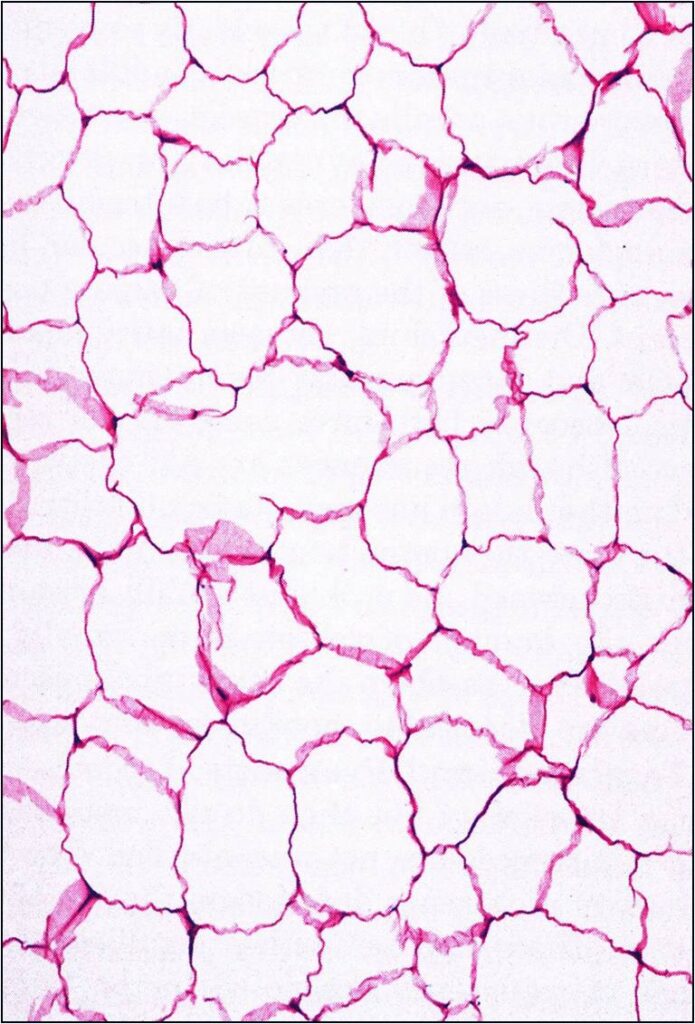

Microscopic

• Mature fat cells with small, uniform, eccentric nuclei

• Nucleus compressed against the periphery of the cell membrane by a fat vacuole

• No mitotic figures

• Can have areas that undergo fat necrosis

• Muscle fibers interspersed amongst mature adipocytes (intramuscular lipomas)

• Other components

• Fibrous tissue

• Myxoid tissue

• Blood vessels

Fig. 4 & 5: Microscopic Pathology of a lipoma shows a homogeneous structure in low and high magnification with a uniform cell pattern and peripheral compressed nuclei barely discernible. Mature adipocytes. No mitoses.